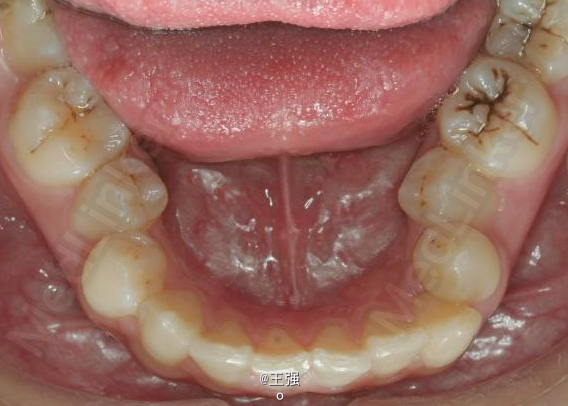

又一例不对称拔牙

牙弓狭窄,牙列拥挤

不对称拔牙